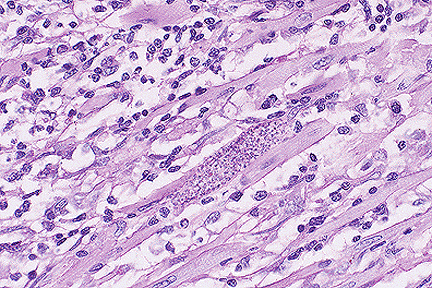

Protozoal cyst of T. cruzi in the heart of a puppy. (40X, HE, 120K)

Contributor's Diagnosis and Comments: Heart: Pancarditis, lymphoplasmacytic and granulomatous, diffuse, chronic, severe, with multifocal cardiomyofiber necrosis, and intrasarcoplasmic protozoal amastigotes, English Pointer, canine.

Diffusely in the endocardium and in the interstitium of the myocardium, there is marked inflammation composed of plasma cells, lymphocytes, macrophages, and lesser numbers of neutrophils, accompanied by moderate perimysial fibrosis. This inflammation widely separates, and multifocally replaces, myocardial fibers. Multifocally, myocardial fiber diameter is decreased, and occasionally fibers are eosinophilic, fragmented, and lack striations. Scattered fibers contain pseudocysts which contain multiple amastigotes, each of which has a basophilic kinetoplast and a nucleus.

AFIP Diagnosis: Heart: Pancarditis, necrotizing, subacute, diffuse, severe, with intrasarcoplasmic amastigotes, English Pointer, canine, etiology consistent with Trypanosoma cruzi.